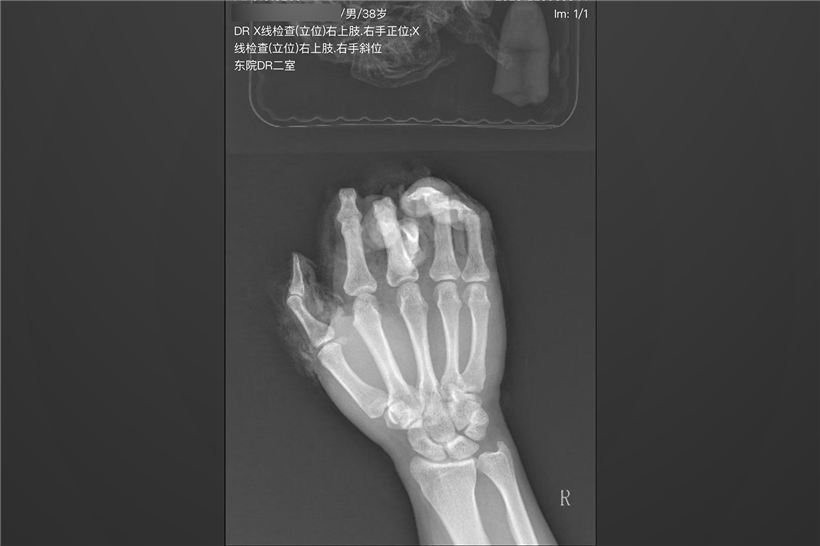

当天早上,吴先生(化名)的右手不慎被机器绞伤,被紧急送到烟台山医院。检查发现,其右手拇指、食指、中指完全离断,且损伤类型极为特殊——并非整齐切断,而是皮肤、软组织像“脱手套”一样,从近端向远端呈现“手套状”撕脱,骨骼、肌腱、血管及神经被暴力抽出,损伤范围巨大,污染严重。

患者的手像被“扒皮抽筋”一样,皮肤软组织从手指上整体撕脱下来。